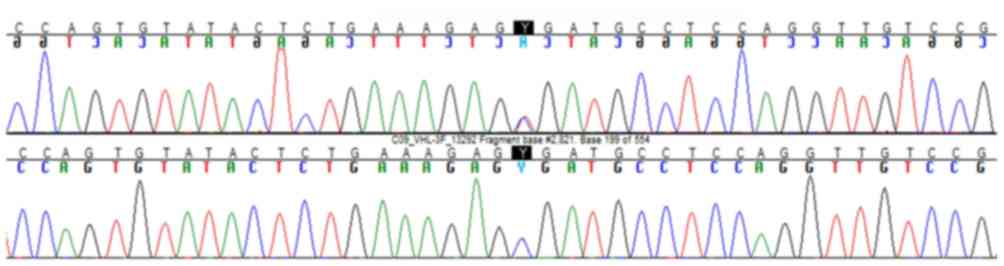

pancreatic cysts, supported the diagnosis of VHLs. Whole blood was

collected for genomic DNA analysis and VHL gene sequencing,

which confirmed VHLs (Fig. 2). The

VHL gene nucleotide sequence was obtained by EMBL Nucleotide

Sequence Database [BBC+00] (http://www.ebi.ac.uk/embl/index.html; ENST00000256196,

sequence: JQ821733). Sequencing was performed by polymerase chain

reaction using the following primers: F: TACTACAGAGGCATGAACACC and

R: CCCCTAAACATCACAATGC. In silico analyses by the mutation

analyzer 2.0.28 (https://mutalyzer.nl) suggested the

pathogenic potential of this variant. Pheochromocytoma was excluded

Our patient harbored a nonsense VHL mutation

(single-nucleotide change causing a premature stop codon in exon 3:

c.481C>T; p.Arg161*) without pheochromocytoma (type 1). What is